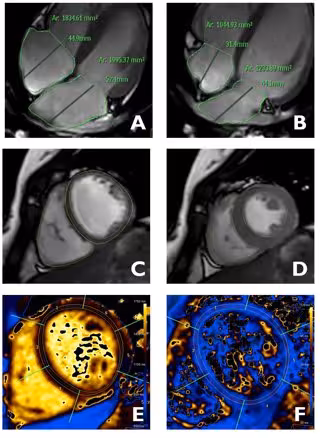

Imágenes del corazón obtenidas mediante resonancia magnética en las que se analizan distintas estructuras de la anatomía y función del corazón: aurículas (A y B), ventrículos (C y D), características del tejido cardiaco (E y F).

Imágenes del corazón obtenidas mediante resonancia magnética en las que se analizan distintas estructuras de la anatomía y función del corazón: aurículas (A y B), ventrículos (C y D), características del tejido cardiaco (E y F). - CNIC

El director científico del CNIC y co-autor del trabajo, Borja Ibáñez, ha asegurado que "los resultados tienen implicaciones directas en la práctica clínica, pues proporcionan un listado de valores de referencia para multitud de parámetros del corazón utilizados en la práctica diaria, como son las dimensiones y función de las diferentes cámaras cardiacas (aurículas y los ventrículos) y la composición del tejido cardiaco".